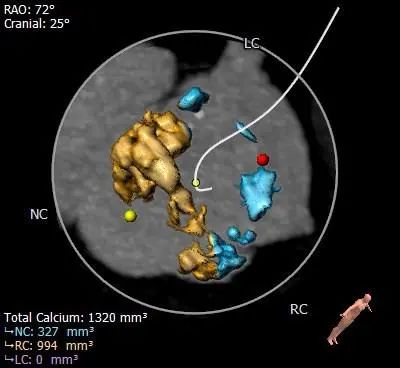

Type 0型二叶式主动脉瓣,重度钙化,无冠窦瓣叶边缘靠近左冠侧钙化较重呈团块状,钙化向对合边缘及流出道延伸,前窦钙化分布于窦内,瓣叶不规则增厚粘连。

HU850

HU1000